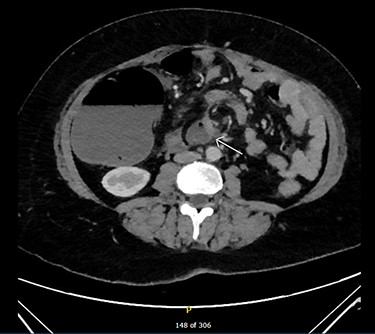

Admission blood tests were unremarkable. Abdominal X-ray showed non-specific signs of large bowel obstruction (Fig. 1). Computed tomography (CT) scan indicated unusual location of the caecum in the right upper quadrant along with gross distension up to 13 cm (Fig. 2), a whirling pattern of mesenteric vessels (Fig. 3) and a competent ileo-caecal valve. In context of her surgical history, these findings raised concern for a closed loop obstruction due to internal herniation.

On CT several particular features are diagnostic for caecal volvulus. The ‘bird’s beak’ sign shows the tapering of proximal and distal portions of bowels progressing towards the point of torsion [6, 7]. However, the most sensitive sign is a particular ‘whirl’ that is characteristic of mesenteric torsion and engorgement of blood vessels around a fixed point [8]. Evidence of this ‘whirl’ along with direction of the twist was 93% sensitive in the determination of caecal compared to sigmoid volvulus [8].